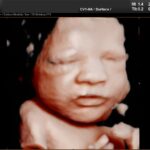

3D/4D ultrazvuk

3D/4D video a foto bábätka s najmodernejším ultrazvukovým prístrojom

vyhotovenie farebných fotiek a nahrávanie záznamov na USB kľúč/DVD